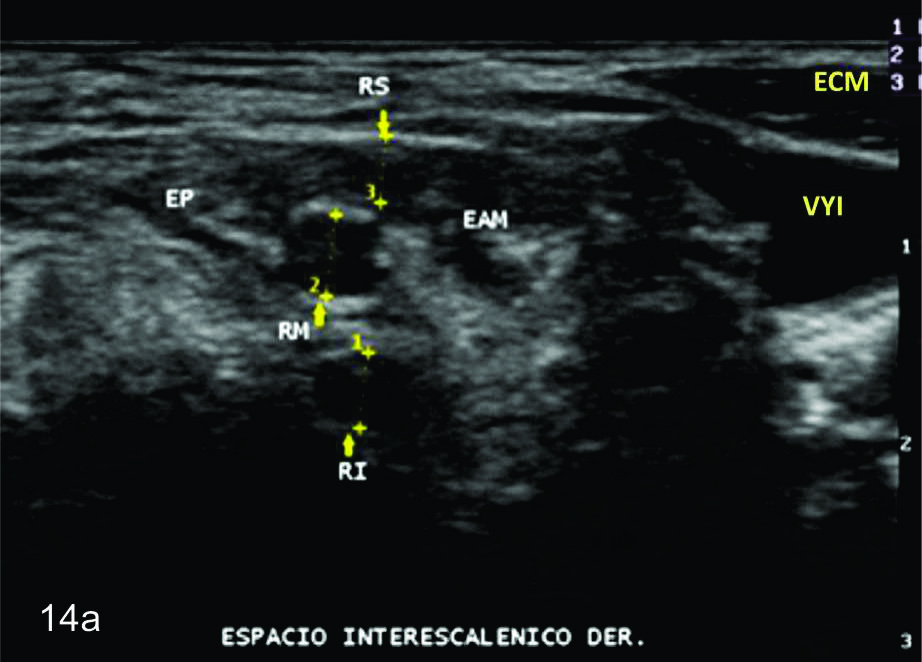

Figura 14 a y b

Lesión traumática del plexo braquial luego de accidente en moto.

A y B- cortes comparativos transversales al plexo braquial al nivel del espacio interescalénico (A-derecho patológico y B-izquierdo sano), se demuestra la asimetría de las estructuras del plexo. RS- tronco superior, RM-tronco medio, RI-tronco inferior, EP- músculo escaleno anterior, EAM-músculos escalenos medio y anterior.